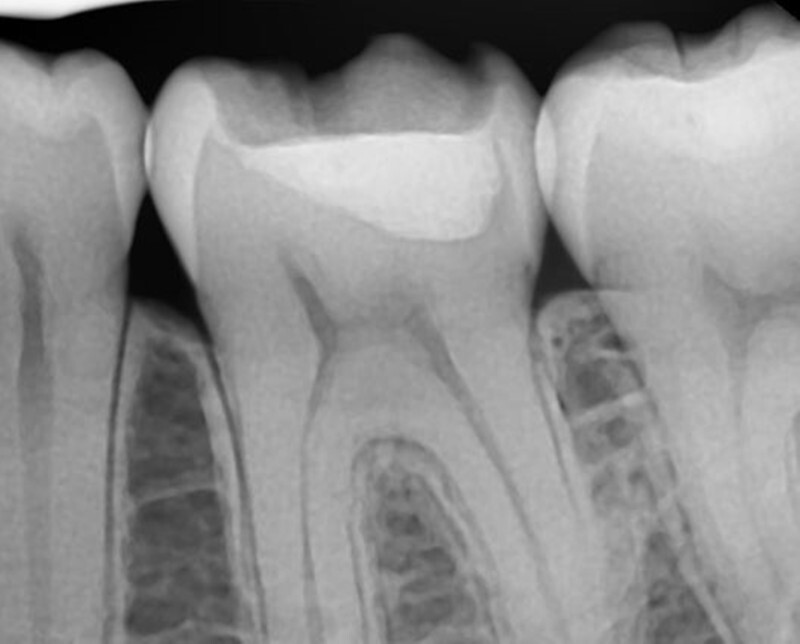

최근에 저는 드디어 치과진료가 끝이 났어요.

올해가 공단 검진 대상자여서 구강검진을 받기 위해

치과에 내원해서 스케일링과 검진을 하던 중에

치아 사이에 큰 충치가 생긴 것을 발견했는데요.

충치 범위도 크고 사이에 위치해 있어서

때우는 치료가 불가능했기 때문에

신경치료를 하고 크라운치료를 받았어요.

치과 공포증이 있던 제가 몇 년 검진을 미루는 사이에

일이 커져버려서 돈도 돈이지만

치료받는다고 정말 맘고생이 많았어요.